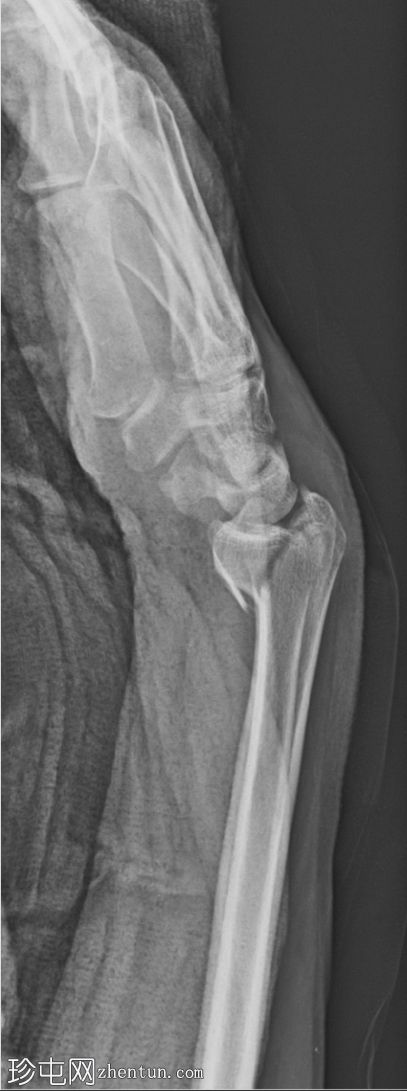

侧位片

可见一条锐利的斜形骨折线延伸至桡骨远端掌侧关节缘

侧位片清晰显示关节内延伸

桡腕关节掌侧半脱位

腕骨对位基本保持良好